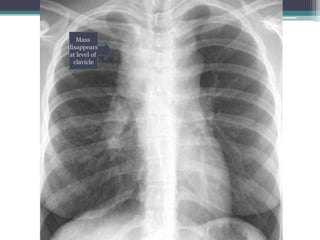

Which compartment do you think this mass is in?

Click for answer

Mass

โ€œdisappearsโ€

at clavicle

Cervicothoracic sign

โ€ข Answer: Mass lies in anterior mediastinum. We

know this because it disappears at the level of the

clavicle where it extends into the neck.

โ€ข This particular example is Non-Hodgkins lymphoma